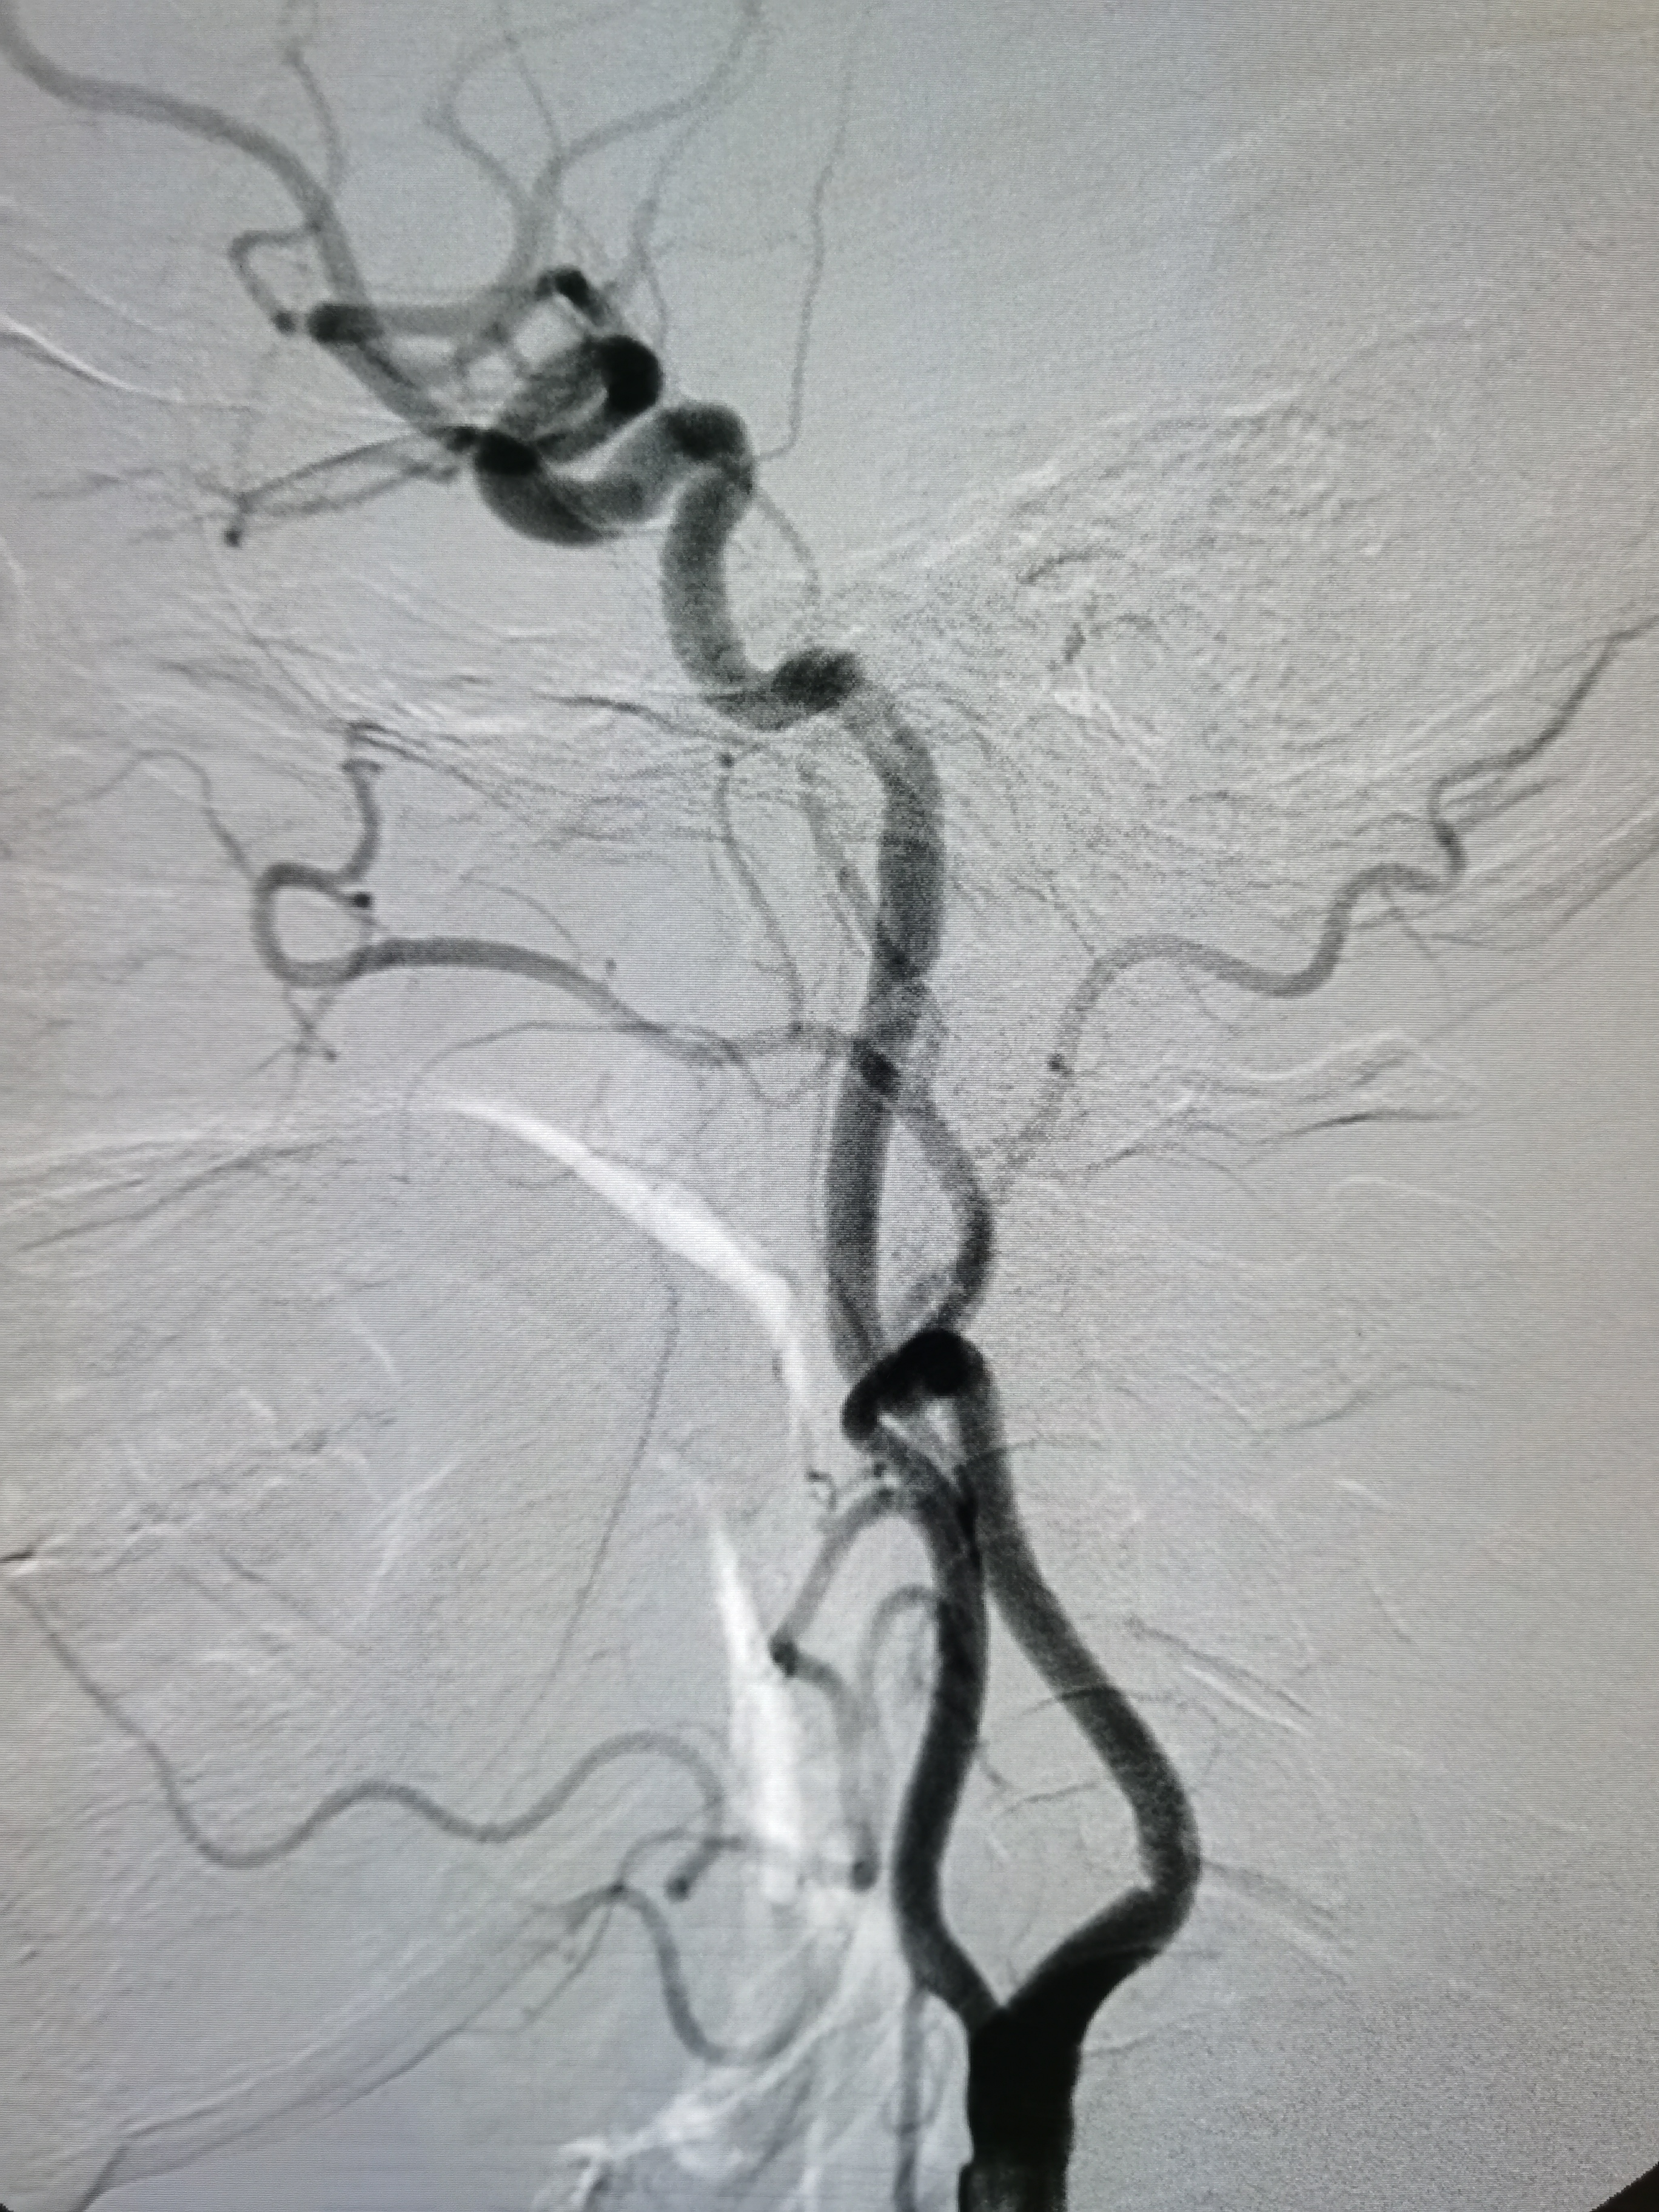

将8F导引导管送至左侧锁骨下动脉近左椎动脉起始部,微导丝顺利通过病变,2.0/20球囊预扩病变。

2、CTA证实左椎动脉起始部重度狭窄合并血栓,系责任血管,存在急性闭塞或残存血栓脱落至基底动脉风险,需积极处理。

3、手术过程中,先用小球囊扩张病变,观察血栓情况,及时应用支架全程覆盖血栓及病变部位,成形满意。